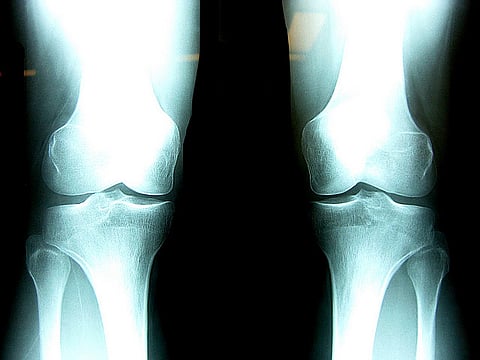

New Bioactive Gel to Treat Knee Injuries

WASHINGTON: Researchers are developing an injectable, bioactive gel to treat knee injuries that encourages self-healing of cartilage.